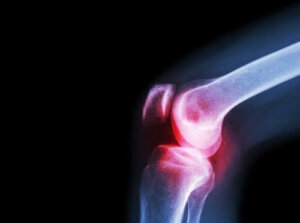

De symptomen van septische artritis variëren afhankelijk van het type infectie. Bacteriële infecties (Engelse link) hebben de neiging om slechts één gewricht te treffen, meestal de knie of heup.

Artsen kunnen ook een röntgenfoto van het aangetaste gewricht maken. Röntgenfoto’s en andere diagnostische beeldvormingshulpmiddelen kunnen helpen om de schade te evalueren.